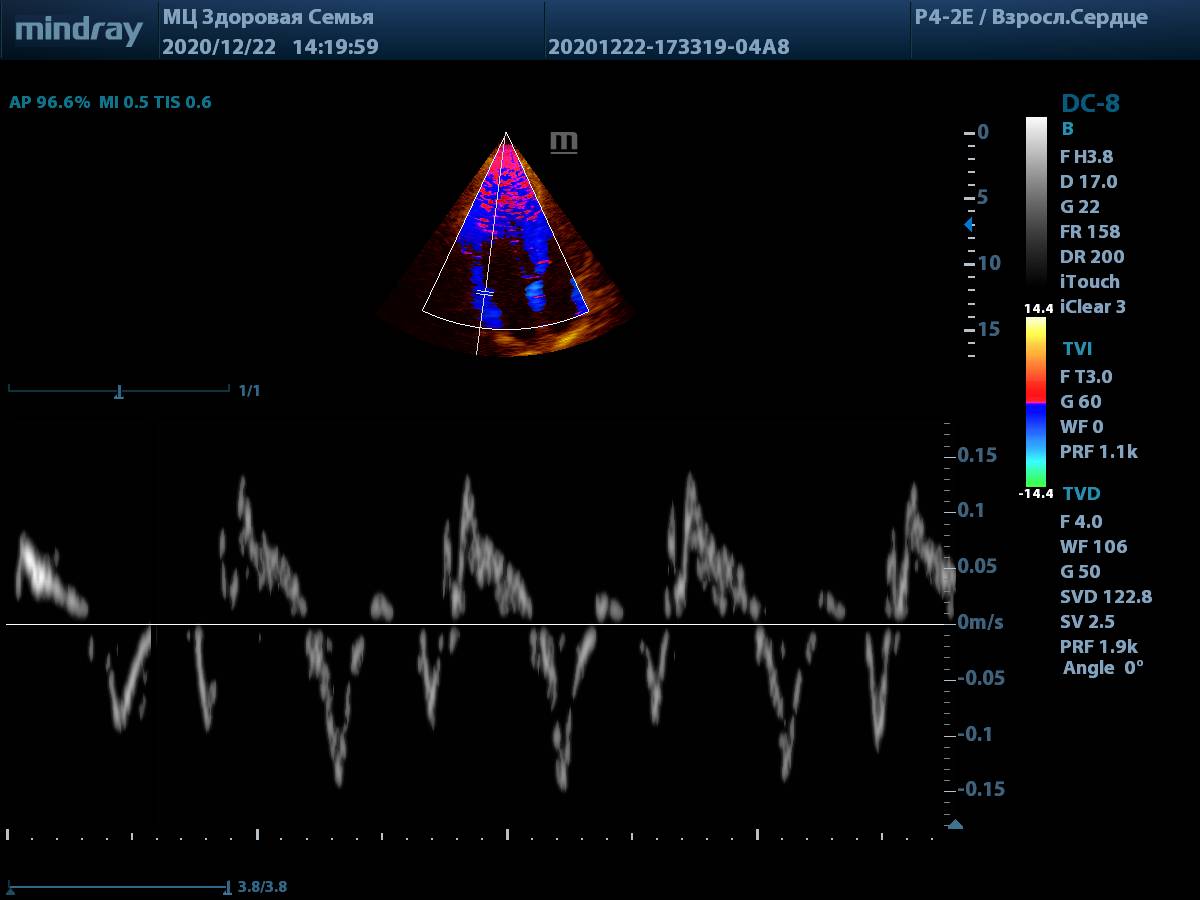

Сегодня мы предлагаем посмотреть на настоящие снимки и видео петли, полученные на живом потоке пациентов. Такие изображения встречаются в клинической практике ежедневно у пациентов без идеального ЭХО окна. Снимки выполнены на аппарате экспертного класса Mindray DC-8.

3. Тканевая допплерография (TDI). Всё просто и удобно, достаточно нажать одну кнопку. Цветовая карта по умолчанию яркая, не нужно настраивать её усиление для выбора точки установки контрольного объема.